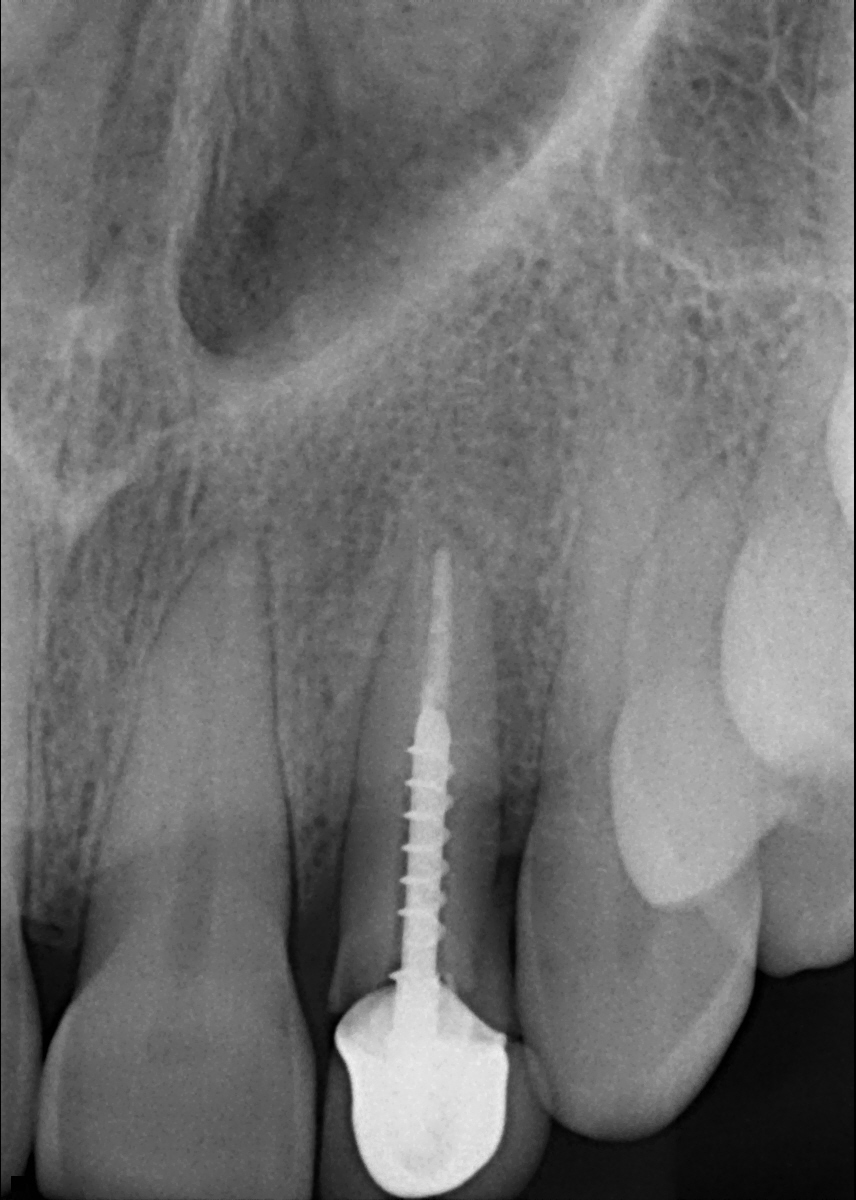

Case #4

Immediate implant.

- Fractured non-sealable tooth needed to be extracted

- Implant placed, restored with permanent crown.